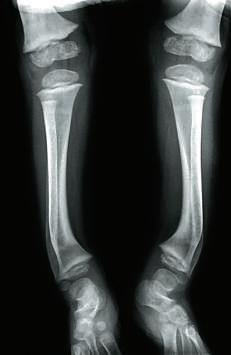

розмір

ся кістковою. За

допомогою якісної

ультразвукової діа-

гностики плода в

Рис. 42.9.